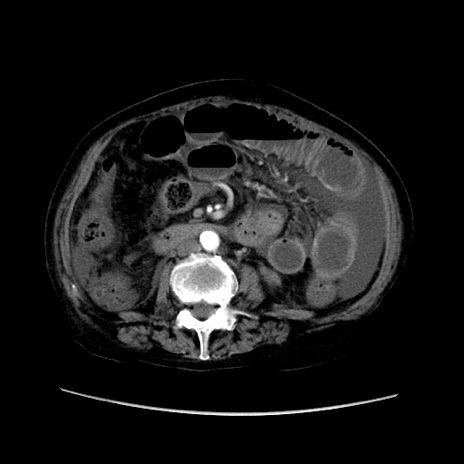

症例31(横断像)

【症例】80歳代 女性

【主訴】腹部膨満感

【現病歴】他院にて肝硬変にてフォロー中。1週間前から便秘、腹部膨満感、臍部腫瘤あり受診となる。

【既往歴】肝硬変

【身体所見】腹部膨隆あり、皮膚変化なし、疼痛なし。

【データ】WBC 4600、CRP 0.25